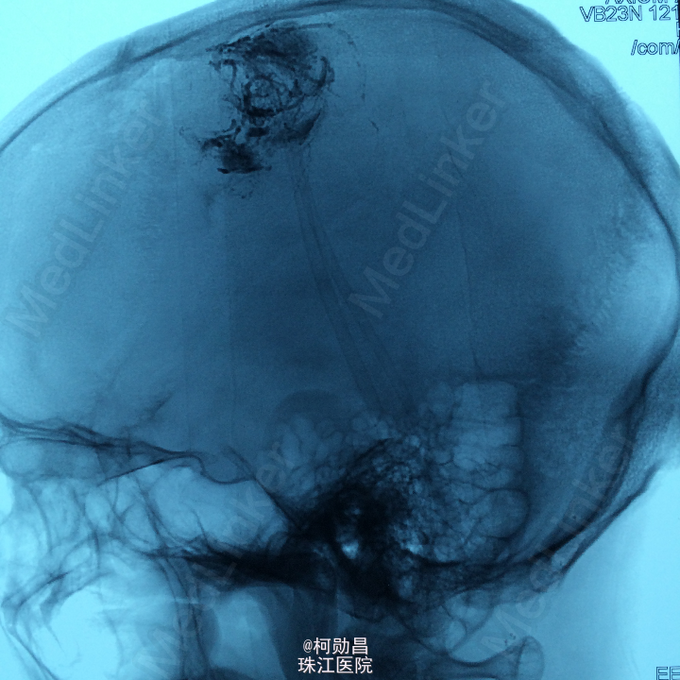

主诉:头痛伴右上肢麻木无力两个月,加重七天 病史:两个月前出现头痛,走路不稳,右上肢无力,不能持物,过去两个月曾有两次癫痫全面发作,发作时意识丧失,但无尿失禁及舌头咬伤。查头MRI示右侧顶叶占位,考虑脑膜瘤。

查体:巴氏征阳性,左侧肢体感觉减退,肌力正常,余无特殊阳性。 辅助检查:查头MRI示右侧顶叶占位,考虑脑膜瘤。

诊断:左侧顶叶占位 处理:行DSA检查,提示肿瘤染色,予PVA颗粒行血管内栓塞治疗。

术后再予开颅手术治疗,书中见供血动脉闭塞,出血量少。